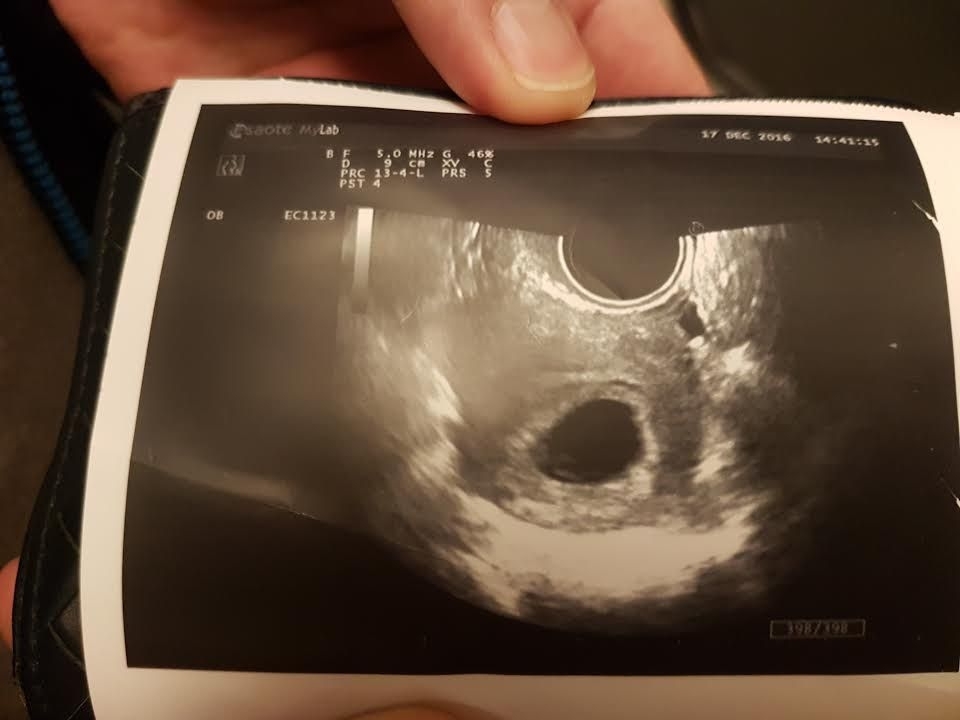

(照片是懷孕大概五周的陰道超音波,確定懷孕,且著床於子宮內,但超音波只照得到黑黑的胚胎)

驗出兩條線之後,喵就掛了婦產科的門診,確認一下寶寶的狀況。

第一次到婦產科報到時,因為周數大概只有五周左右,醫生是用陰道超音波證實有胚胎的狀態

同時也很正確的著床在子宮的位置(如果不是就是子宮外孕,孕婦會有危險)

第一張超音波照片只有一個黑黑的影子,醫生說那是寶寶先蓋起來的房子,寶寶還太小看不到。